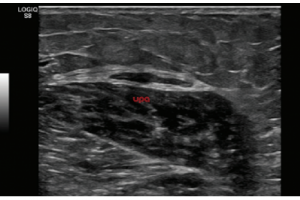

- Аппарат ультразвуковой диагностики Logiq S8

- Система Logiq S8 GE Healtcare, производства Россия – это уникальная ультразвуковая система экспертного класса, компактная и мобильная, удобная в эксплуатации.

Аппарат Logiq S8